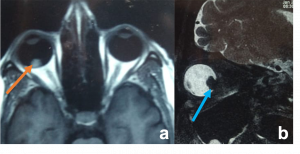

| Carotid-Cavernous Fistula[25] | No age/ gender predilection | Direct – sudden pulsatile exophthalmos, conjunctival chemosis, with dilated episcleral vessels and bruit.

|

USG Doppler – shows increased velocity with reversal of blood flow direction, dilated Superior Ophthalmic Vein (SOV) and arterial pulsations.

CT/MRI - proptosis, EOM enlargement, dilated and tortuous SOV, with engorgement and early enhancement of the ipsilateral cavernous sinus. CT Angiography- differentiate direct and indirect CCF but cerebral angiography is used for accurate diagnosis and intervention. |

Traumatic carotid-cavernous fistula) Axial T2WI MRI of right orbit showing dilated superior ophthalmic vein along its whole course (orange arrow) b) Coronal T2WI MRI showing dilated superior ophthalmic vein (white dotted arrow) with engorgement of the extra ocular muscles compared to the contralateral normal side (orange arrows) |